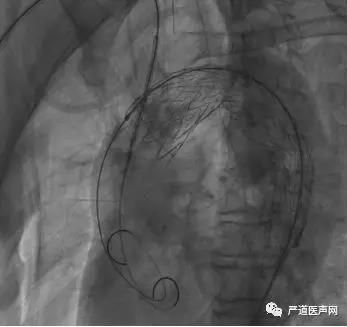

然后继续释放头臂干烟囱支架(如下图),

释放成功后再送入猪尾导管于升主动脉复查造影,结果提示支架贴壁良好,主动脉隔绝良好,头臂干及弓上血管血流通畅,未见明显内漏(如下图)。

关于主动脉覆膜支架的选择,由于弓部弯曲的几何特征,支架释放后容易导致逆撕和鸟嘴征,故本例手术选用了柔顺性好的戈尔主动脉覆膜支架系统。术后造影提示支架贴壁良好,无内漏及鸟嘴征,这一结果获得在场专家的高度赞扬。